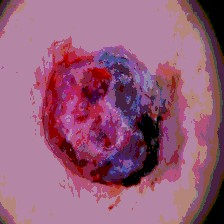

Timely identification and treatment of rapidly progressing skin cancers can significantly contribute to the preservation of patients' health and well-being. Dermoscopy, a dependable and accessible tool, plays a pivotal role in the initial stages of skin cancer detection. Consequently, the effective processing of digital dermoscopy images holds significant importance in elevating the accuracy of skin cancer diagnoses. Multilevel thresholding is a key tool in medical imaging that extracts objects within the image to facilitate its analysis. In this paper, an enhanced version of the Mud Ring Algorithm hybridized with the Whale Optimization Algorithm, named WMRA, is proposed. The proposed approach utilizes bubble-net attack and mud ring strategy to overcome stagnation in local optima and obtain optimal thresholds. The experimental results show that WMRA is powerful against a cluster of recent methods in terms of fitness, Peak Signal to Noise Ratio (PSNR), and Mean Square Error (MSE).